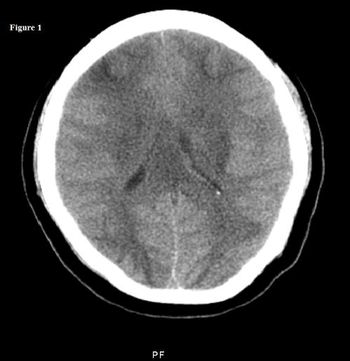

An unusual cause of postpartum neurologic deficits: MRIs of progressing relapsing-remitting MS; Lhermitte-Duclos disease as a cause of ataxia: here. . . 5 short clinical cases, each with images, that offer take-home messages you can use in your practice.